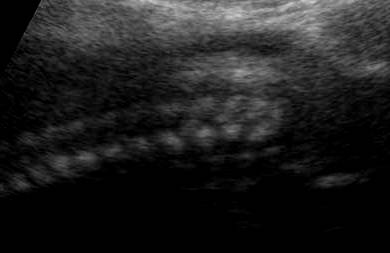

E' caratterizzata da deficit di vario grado di tutti e quattro gli arti (assenza di ulna e fibula con assenza o deficit severo degli arti come focomelia, oligodattilia, etc.), con ipoplasia o agenesia delle ossa del bacino (anche ipoplasia o agenesia del sacro), anomalie genitali consistenti in agenesia dell'utero e della vagina, micropene.

La diagnosi ecografica si basa principalmente sulle anomalie degli arti  e sull'agenesia del sacro.